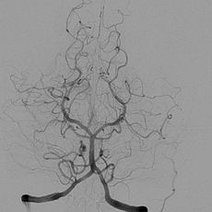

- 数字减影血管造影技术,颅内动脉瘤介入治疗,湘雅护理学院,颅内动脉瘤,颅内动脉瘤系指脑动脉壁的异常膨出部分,是引起自发性蛛网膜下腔出血的最常见原因。病因-尚不甚清楚,但以先天性动脉瘤占大部分。任何年龄可

- 颅内动脉瘤介入治疗的护理,主讲人杨鑫,。,一、概述颅内动脉瘤时由于局部血管异常改变产生的脑血管样突起。其主要症状多由出血引起,部分因瘤提压迫,动脉痉挛及栓塞造成。,,,,,,,,,,,,二、颅内动脉瘤介入适应症和禁忌症适应症、几乎所有的动脉

- 动瘤DavidSLiebeskind1引1.1景动瘤是有破倾向的管结构的病理性局灶性扩张。些管异常常根据假定的病因分类。囊状、浆果状或先天性动瘤占全动瘤的90